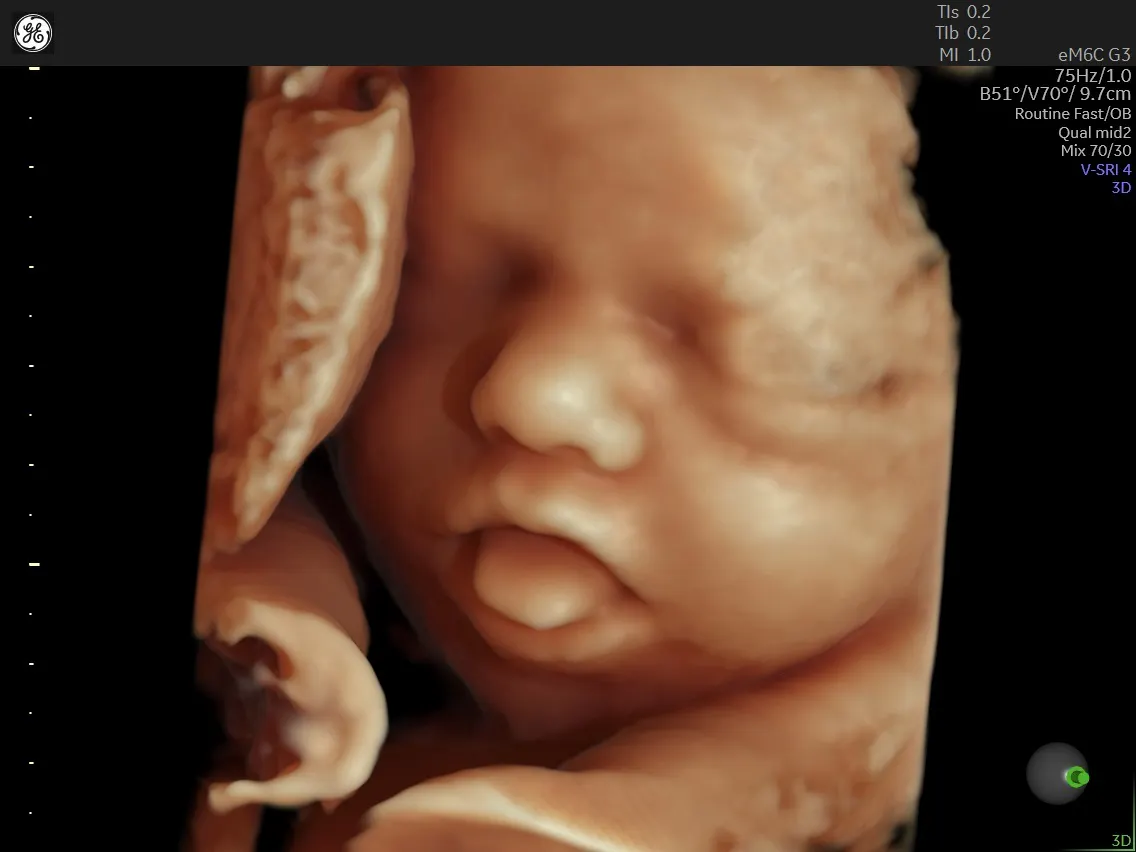

Maternal Fetal Medicine drtsoumpou.gr

Maternal Fetal Medicine drtsoumpou.gr Winchester Hospital Maternal Fetal Medicine Our experienced team provides the full range of services for the duration of your pregnancy, delivery and after the birth of your baby,. Linda c kleeman, md is affiliated with lahey health and specializes in maternal. Learn about the team, services, and location of. Valley health provides pregnancy, birth, breastfeeding and maternal fetal medicine services at winchester medical center and.. Winchester Hospital Maternal Fetal Medicine.